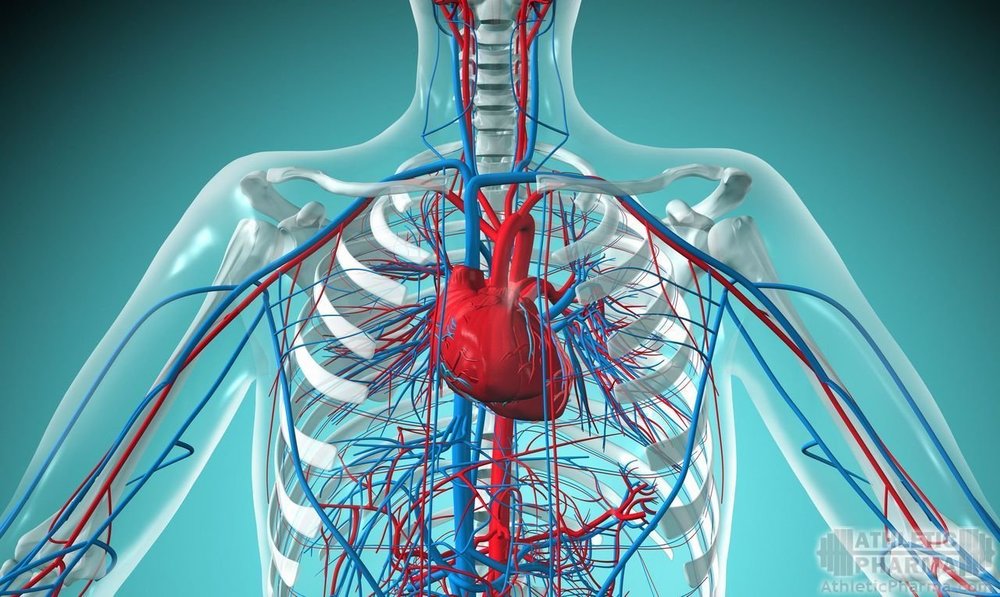

Независимо от целей, злоупотребление стероидами является фактором риска сердечно-сосудистых заболеваний. Многие профессиональные качки, кто на еженедельной основе использует по несколько грамм тестостерона, нандролона или тренболона и десятками поедает таблетки метандиенона, заправляя этот компот гормоном роста и инсулином для надежности, не хотят мириться с подтвержденным исследованиями и статистикой фактом. Зачем они лгут сами себе – наука пока не определила…

Такими же факторами риска являются курение, ожирение и семейная история кардиоваскулярных болезней. Все они могут сопровождаться ужасным липидным профилем, сгущением крови, повышенным кровяным давлением, увеличенным ЧСС, желудочковой гипертрофией и неестественно высокой массой тела.

Большинство поклонников железного спорта ведет физически активный образ жизни, что, как правило, сопровождается правильным питанием и выливается в низкий уровень телесного жира. При всем при этом от сердечно-сосудистых заболеваний они умирают ненамного реже (или также часто), чем остальное население, которое убивает себя вредными привычками. Обжорство – та же вредная привычка. О чем это говорит? О том, что в жизни качков присутствует уникальный фактор риска, который сводит на нет практически всю пользу физически активного образа жизни для сердца и сосудов.

Побочные эффекты стероидов: сердечно-сосудистые риски

Начнем с того, что перечислим факторы риска и побочные эффекты для кардиоваскулярной системы (расскажем обо всем подробно, а главное, простым языком). Ведь предупрежден – значит вооружен!